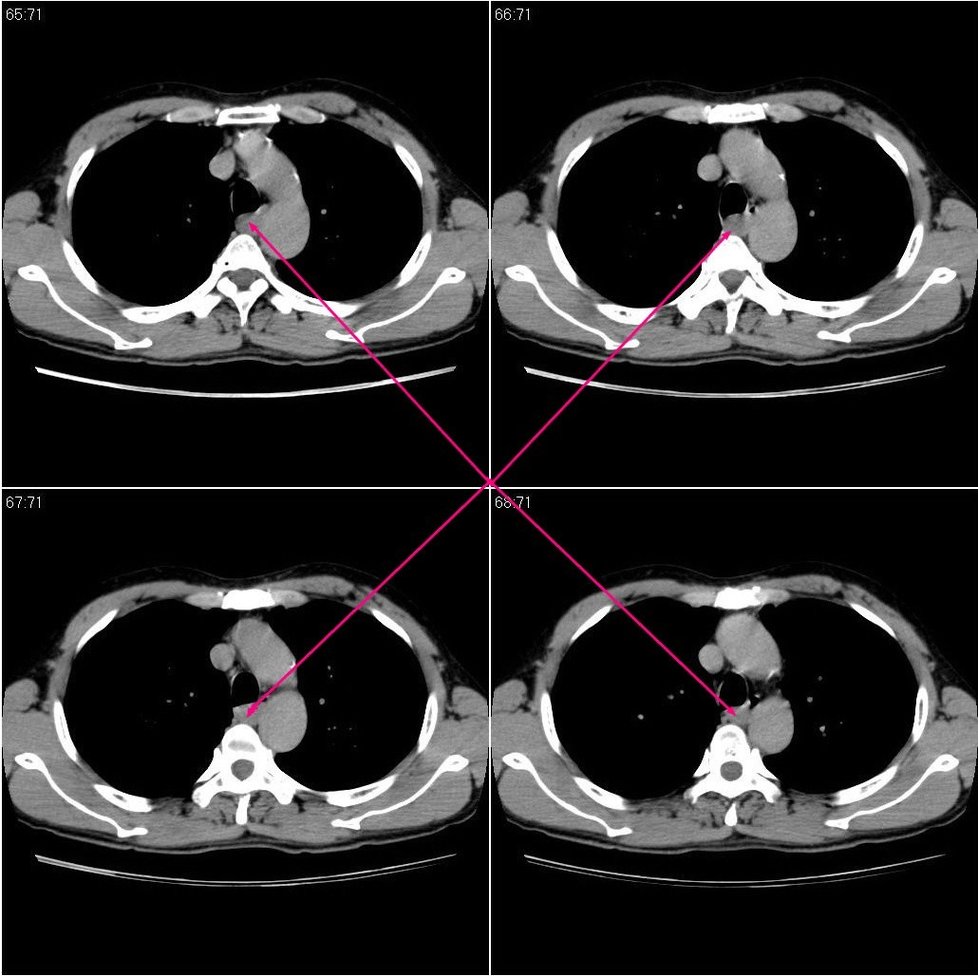

标题: CT20825:男性,46岁。体检时发现食道上段外压性改变。 [打印本页]

标题: CT20825:男性,46岁。体检时发现食道上段外压性改变。

随后患者做了ct平扫和增强:

神经源性肿瘤基本可以排除,因为病变没有强化。现在的问题是,病变考虑不考虑肿大淋巴结呢?因为病变的环周也没有强化,我们的意见也不考虑。这样的话,患者就需要手术处理了。希望高手还能谈谈各自的高见!